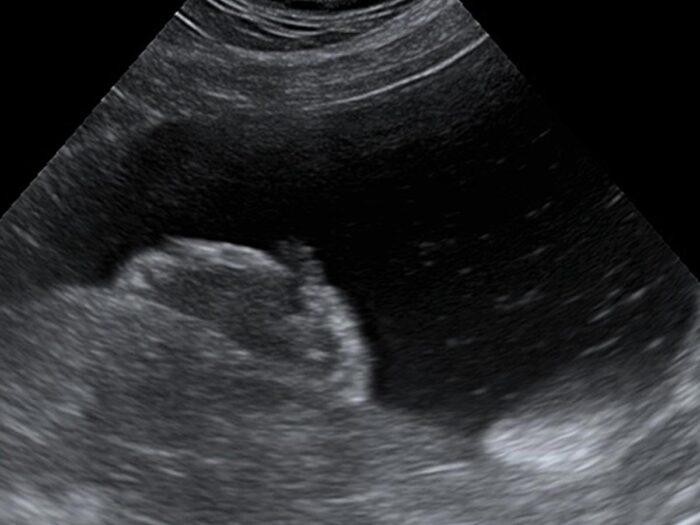

Ultraschallbild eines Harnblasenkarzinoms

BRAF-Mutation und BRAF comp. Test – ein Update

Erfahren Sie alles über die BRAF-Mutation und den BRAF comp. Test beim Hund – wie diese Tests zur Diagnose von Karzinomen der Harnblase und Prostata beitragen.